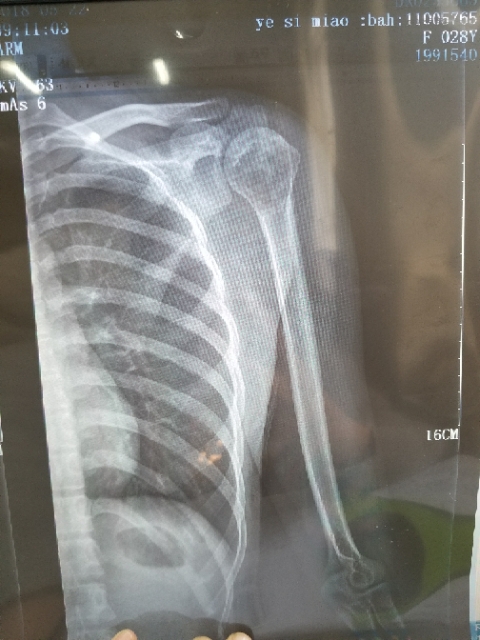

身心俱疲斗争 02019-02-22 患者家属女儿14岁,明天做截肢手术。医生让从髋关节处截,想保留个七八公分。问问大神们髋关节以下留七八公分能用常规的假肢吗? ...

一路向北 02019-01-28 患者家属我孩子今年15岁,年初查出骨肉瘤,左腿关节处,化疗5次做载肢,手术后伤口感染误了化疗,两个多月快三个月发生肺转,如今刚住...

X-man 02019-01-22 患者本人十九岁,九月十号因恶性骨肉瘤在云南省肿瘤医院做了截肢手术,后发现肺上有三个结节,一个大约一厘米,两个不足一厘米,请问...